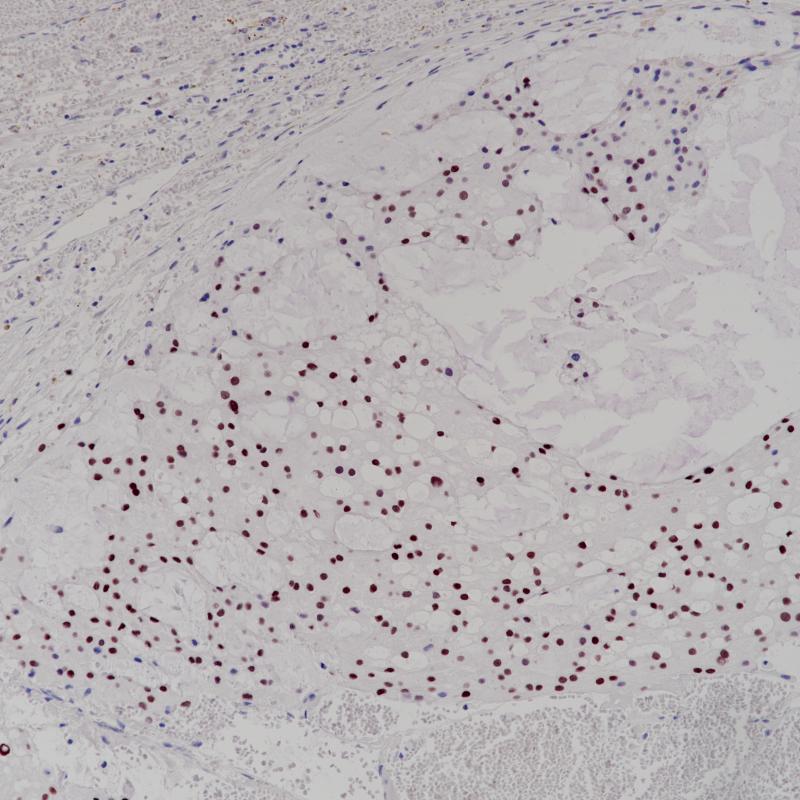

脊索瘤Brachyury(BP6218)染色(2)

Brachyury蛋白由T基因编码,是一种转录因子,在脊椎动物胚胎发生过程中对后中胚层的形成和轴向发育至关重要。人类短肢在脊索以及沿脊柱发生的脊索瘤中表达,使其成为脊索和脊索衍生肿瘤的良好标记。人类T基因的一种常见多态性也被证明与多因素神经管缺损、脊柱裂的发展有关。

阳性对照

脊索瘤

亚细胞定位

细胞核